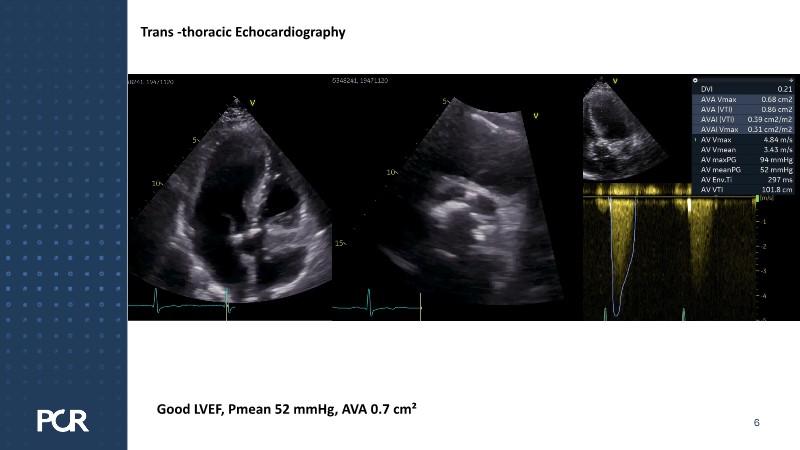

This session examines these crucial aspects through the case of a 77-year-old male with bicuspid aortic valve stenosis, HFpEF and multiple comorbidities, including diabetes, obesity and sleep apnoea.